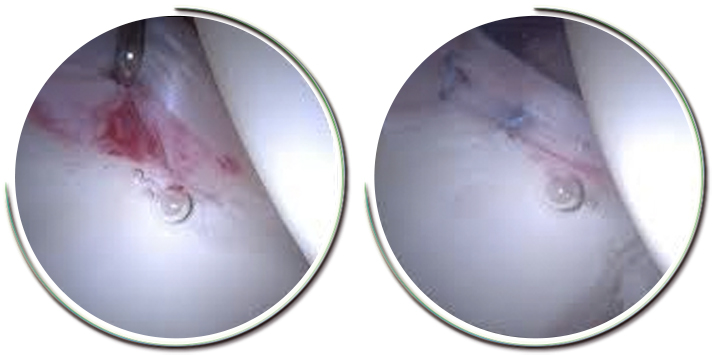

Tedavi için ekleme zarar vermeyen artroskopik cerrahi kullanılabilir. 2 ya da 3 delik kullanılarak eklemdeki yırtık temizlenebilir. Bazen yırtıklar tamir edilmeye uygun niteliktedir, bu durumda yırtık doku arkasında dikişler bulunan çapalarla kemiğe tespit edilir .Kalça artroskopisi ameliyatı için tıklayınız.